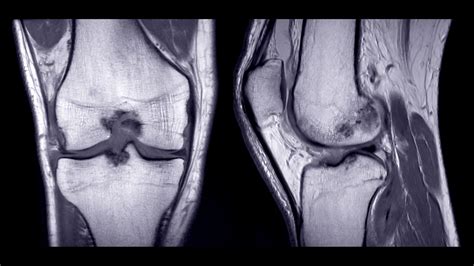

If you have recently experienced persistent joint pain, instability, or a specific injury, your healthcare provider may have recommended a diagnostic scan to get a clearer picture of what is happening inside your joint. Knee MRI images are the gold standard in diagnostic imaging for soft tissue injuries, providing incredibly detailed views that X-rays simply cannot match. Unlike X-rays, which primarily show bone structure, magnetic resonance imaging (MRI) uses powerful magnets and radio waves to create cross-sectional images of the ligaments, tendons, cartilage, and muscles that stabilize your knee. Understanding what these images show and why they are necessary can help demystify the diagnostic process and prepare you for your appointment.

Interpreting knee MRI images is a skill reserved for radiologists, who analyze the scan and produce a detailed report for your referring physician. However, having a basic understanding of what they are looking for can help you better understand your diagnosis. Radiologists look for changes in signal intensity; healthy tissue typically appears in a predictable pattern, while injured or diseased tissue will show up as "brighter" or "darker" areas, known as signal abnormalities.

Bone (Cortical) Appears as a dark outer edge due to low water content.

Ligaments & Tendons Normally appear very dark (low signal) in all imaging sequences.

Meniscus Typically dark; bright signal within the meniscus often indicates a tear.

Joint Fluid Appears dark on T1-weighted images and bright on T2-weighted images.

Bone Marrow Variable signal intensity depending on fat and water content.

When you receive your results, the radiologist’s report will describe these findings in technical terms. For instance, they might describe a high-signal intensity within the meniscus, which suggests a possible tear, or they may note the presence of an effusion, which is an excess accumulation of fluid in the joint, often indicating inflammation or injury.